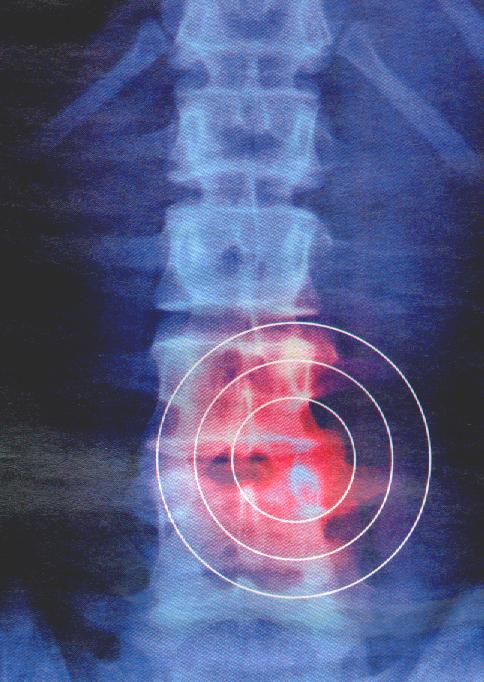

Votre dos vous fait souffrir depuis un certain temps et votre médecin traitant commande une imagerie par résonance magnétique (IRM). Le radiologiste confirme une « discarthrose dégénérative multi-étagée ».

La douleur peut persister à cause d’un dysfonctionnement du système nerveux responsable de la douleur, mais après un certain temps le système immunitaire finit par éliminer les morceaux du noyaux qui se sont infiltrés à l’extérieur de l’anneau cartilagineux.